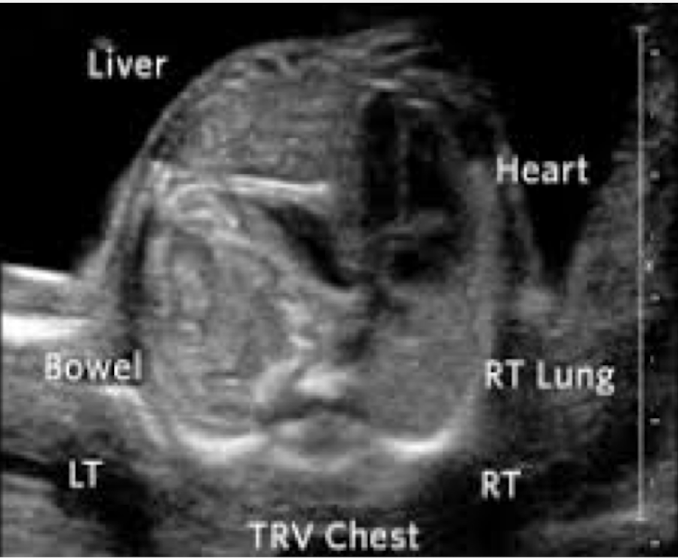

what is this?

diaphragmatic hernia